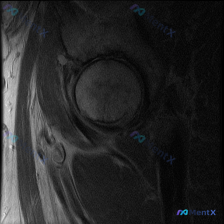

最近整理到一个髋关节MRI影像分析的病例,患者临床怀疑盂唇病变,但提供的单张T1轴位片未显示明确异常。报告详细分析了解剖结构、病变可能性、诊断路径等内容,其中有几个点比较值得讨论: 1. 单张T1轴位片对盂唇病变的敏感性如何? 2. 影像阴性但临床高度怀疑时,下一步应如何评估? 3. 盂唇病变的诊断...

看到一个髋关节MRI评估病例,患者因髋部症状(疼痛、弹响等)行检查,目前只提供了T1轴位序列图像。图像显示盂唇形态完整、信号连续,未见撕裂、退变等明显病理改变。但T1序列存在局限性,对细微损伤不敏感。 大家怎么看这个病例?您认为盂唇病变的可能性大吗?需要进一步做哪些检查?